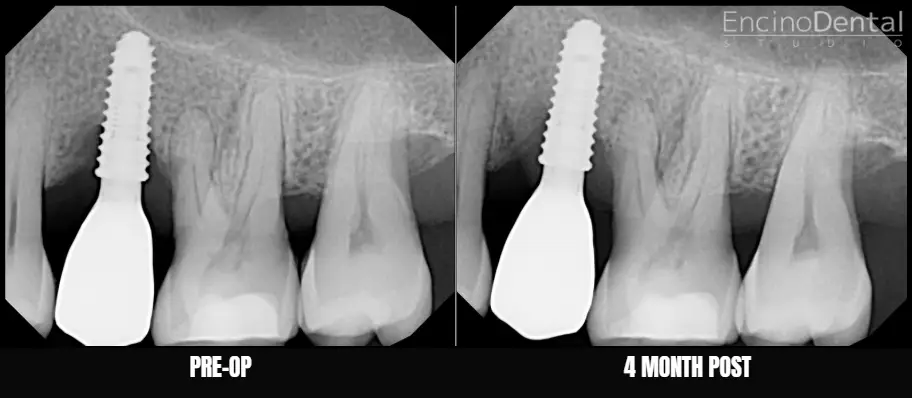

Before and After LAPIP at Encino Dental Studio